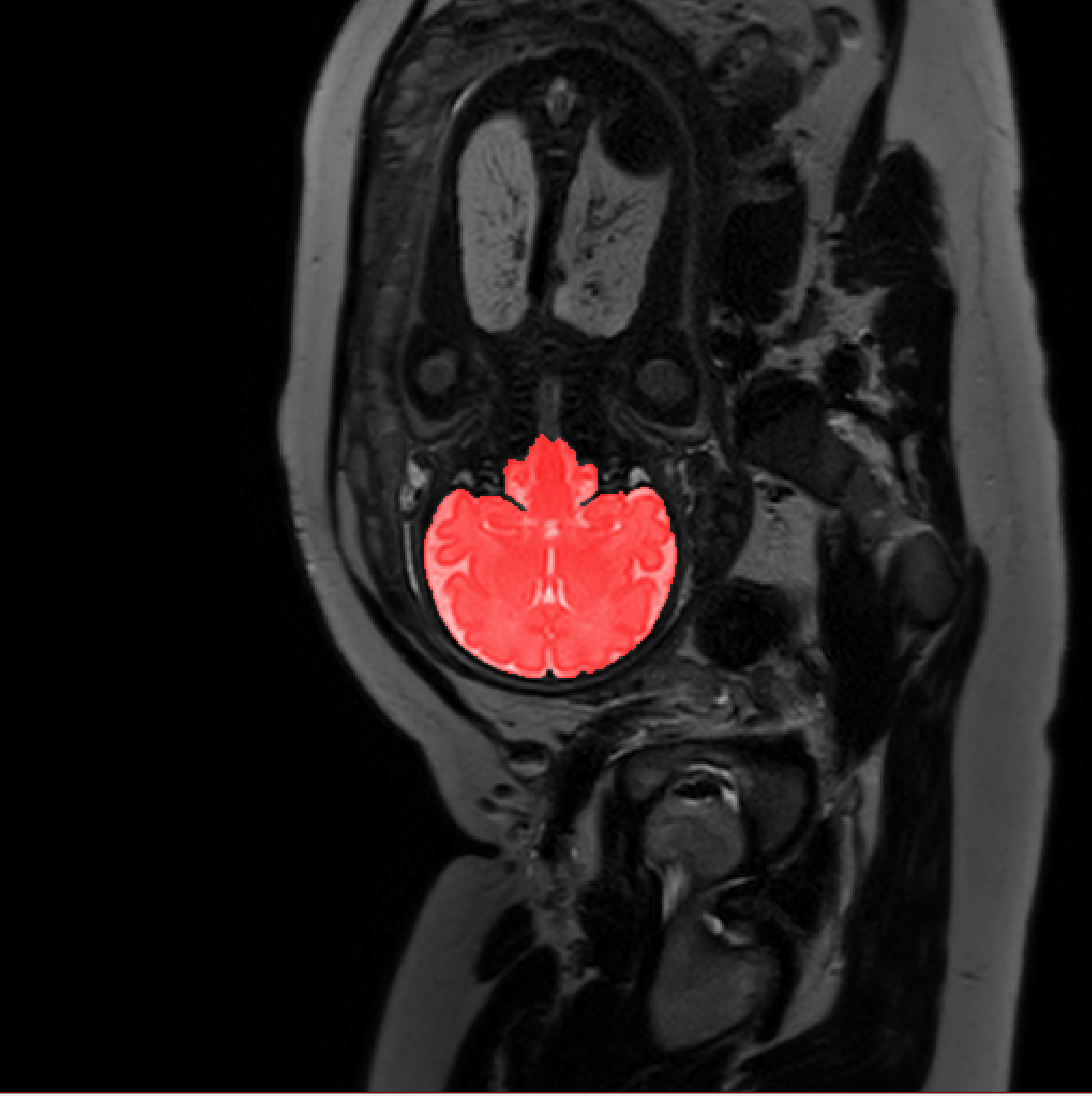

Refer to caption

Figure 3: Example of ICV segmentations in images acquired in axial (left), coronal (middle) and sagittal (right) planes. Top row: A slice from T2-weigted image; Second row: Automatic segmentations obtained using 7 training images from the representative imaging planes; Third row: Automatic segmentations obtained using all 21 training images from all 3 image orientations; Bottom row: Manual segmentation.